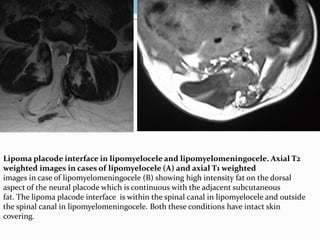

Lipoma placode interface in lipomyelocele and lipomyelomeningocele. Axial T2

weighted images in cases of lipomyelocele (A) and axial T1 weighted

images in case of lipomyelomeningocele (B) showing high intensity fat on the dorsal

aspect of the neural placode which is continuous with the adjacent subcutaneous

fat. The lipoma placode interface is within the spinal canal in lipomyelocele and outside

the spinal canal in lipomyelomeningocele. Both these conditions have intact skin

covering.